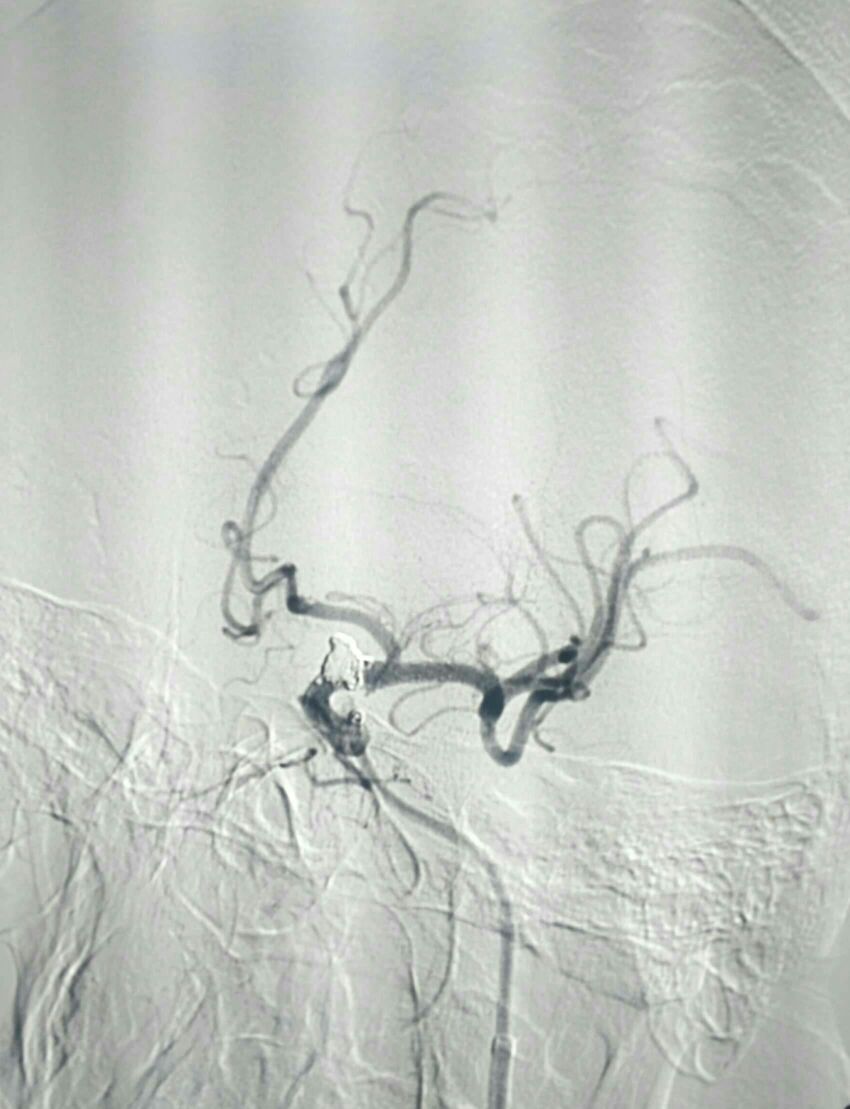

可见原双层支架打开良好

术后20天复查造影动脉瘤栓塞良好无复发显影。目前四肢活动正常,不完全运动性失语,继续康复!

侧位

显示支架

复查3D